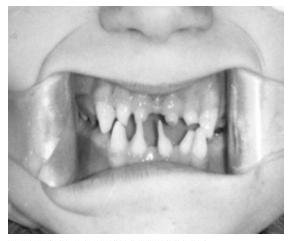

Сверхкомплектные зубы – избыточные по количеству зубы. Они располагаются чаще всего в области фронтальных зубов и чаще имеют шиповидную форму, но могут походить на соседние зубы. В определении лечебной тактики учитывается расположение лишнего зуба и его влияние на положение комплектных зубов. В случае смещения соседних зубов сверхкомплектные зубы удаляют и проводят соответствующее ортодонтическое лечение. Однако возможно и сохранение сверхкомплектного зуба в том случае, если он расположен в дуге и не оказывает отрицательного влияния на соседние зубы, форму коронки при этом можно исправить протезированием.

Транспозиция зубов – перестановка зубов в зубном ряду. Скученное расположение зубов. При этой аномалии зубы располагаются очень тесно, при этом они стоят в повернутом по оси положении и налегают друг на друга.